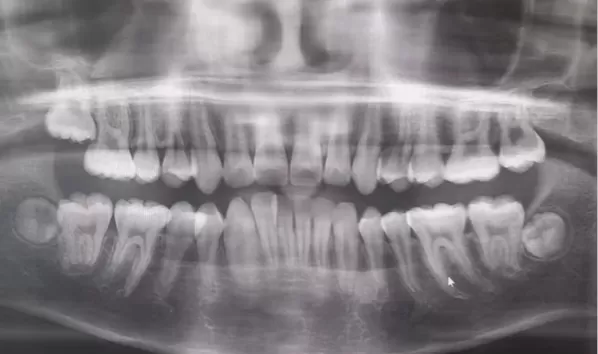

X-rays before treatment

[Panoramic Radiography/Lateral Cephalogram]